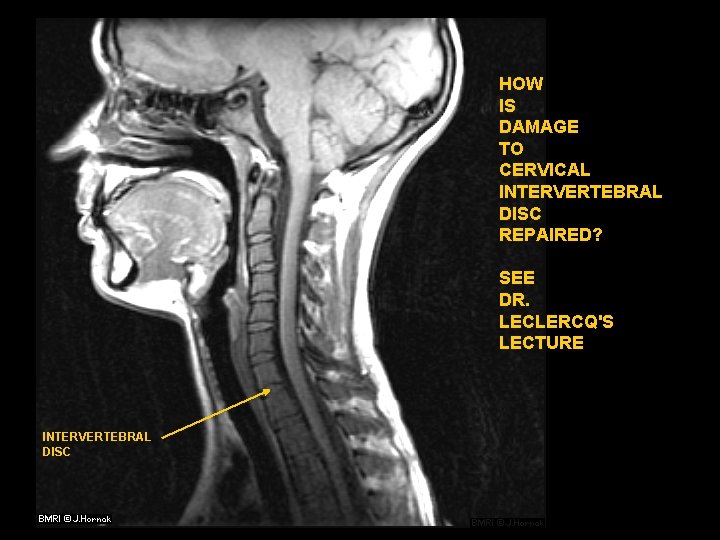

HOW IS DAMAGE TO CERVICAL INTERVERTEBRAL DISC REPAIRED? SEE DR. LECLERCQ'S LECTURE INTERVERTEBRAL DISC